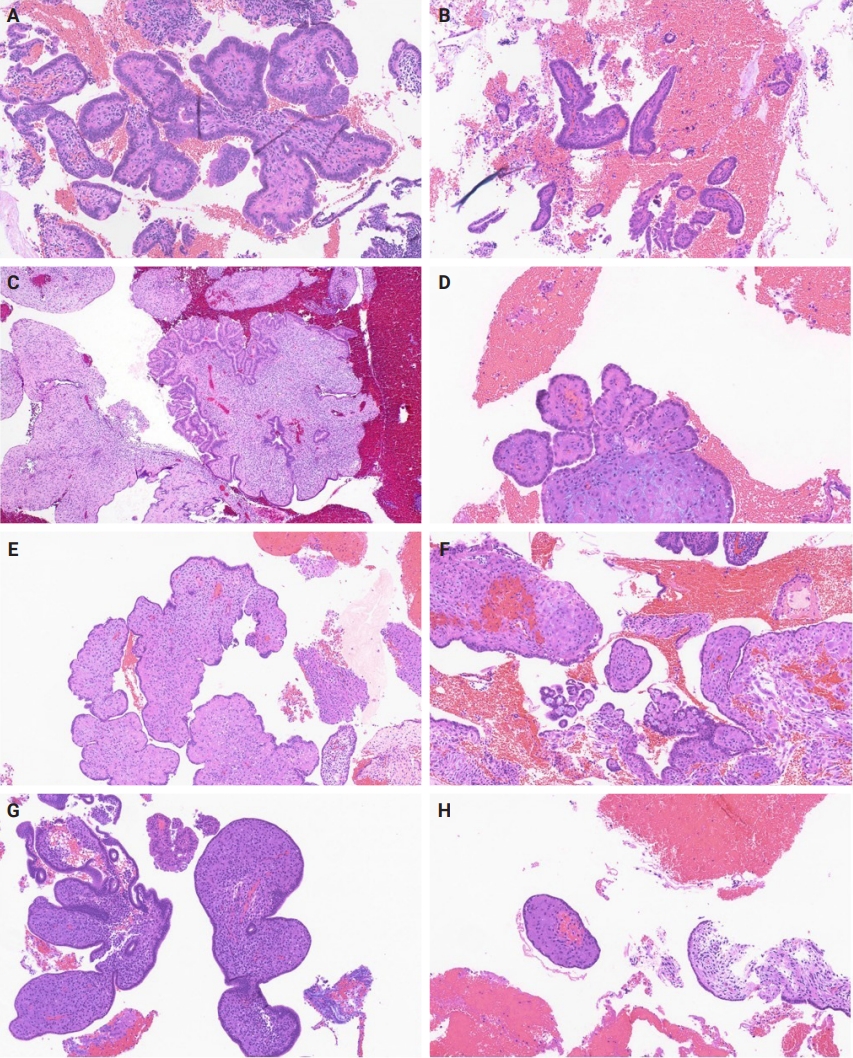

Fig. 2.

Morphologic spectrum of papillae with morphologic variations (A–H).

Slides for all samples (mean, 3.0 ± 2.5 slides/patient) were retrieved and reviewed jointly by the authors, inclusive of the index and all follow-up samples, with the aim of identifying the presence of papillary architecture of any type, describing their morphologic spectrum, and any concurrent pathological processes that may be present. For every case, we documented the presence of papillary structures and estimated the proportion of the specimen that they represented. A papillary structure was defined as a round, oval or filigree structure, at least 75% covered by epithelium, and harboring a stromal or fibrovascular core (Fig. 2). Large bulbous, polypoid structures with prominently pseudodecidualized stroma were not included, given that it is well recognized that such structures are common endometrial alterations associated with exogenous progestins in non-hyperplastic endometrium (Fig. 3) [17,18]. Additionally, we documented for each sample the presence of papillae branching as a surrogate indicator of architectural complexity, with subcategorization to no branching, simple (one level) branching off a central stalk irrespective of the number of such branches, and complex (≥two level) branching (i.e. the presence in the sample of at least one central stalk that gives rise to a primary branch, from which a secondary and possibly tertiary branch originate). We also evaluated other morphologic features that are relevant to the diagnoses of AH/EIN, including glandular crowding, cytologic demarcation/atypia, intraglandular architectural complexity, squamous morules, metaplastic changes, cystic structures (presence, whether they are crowded, and whether they are lined by atrophic-appearing or non-atrophic appearing epithelium), and pseudodecidual stromal change.